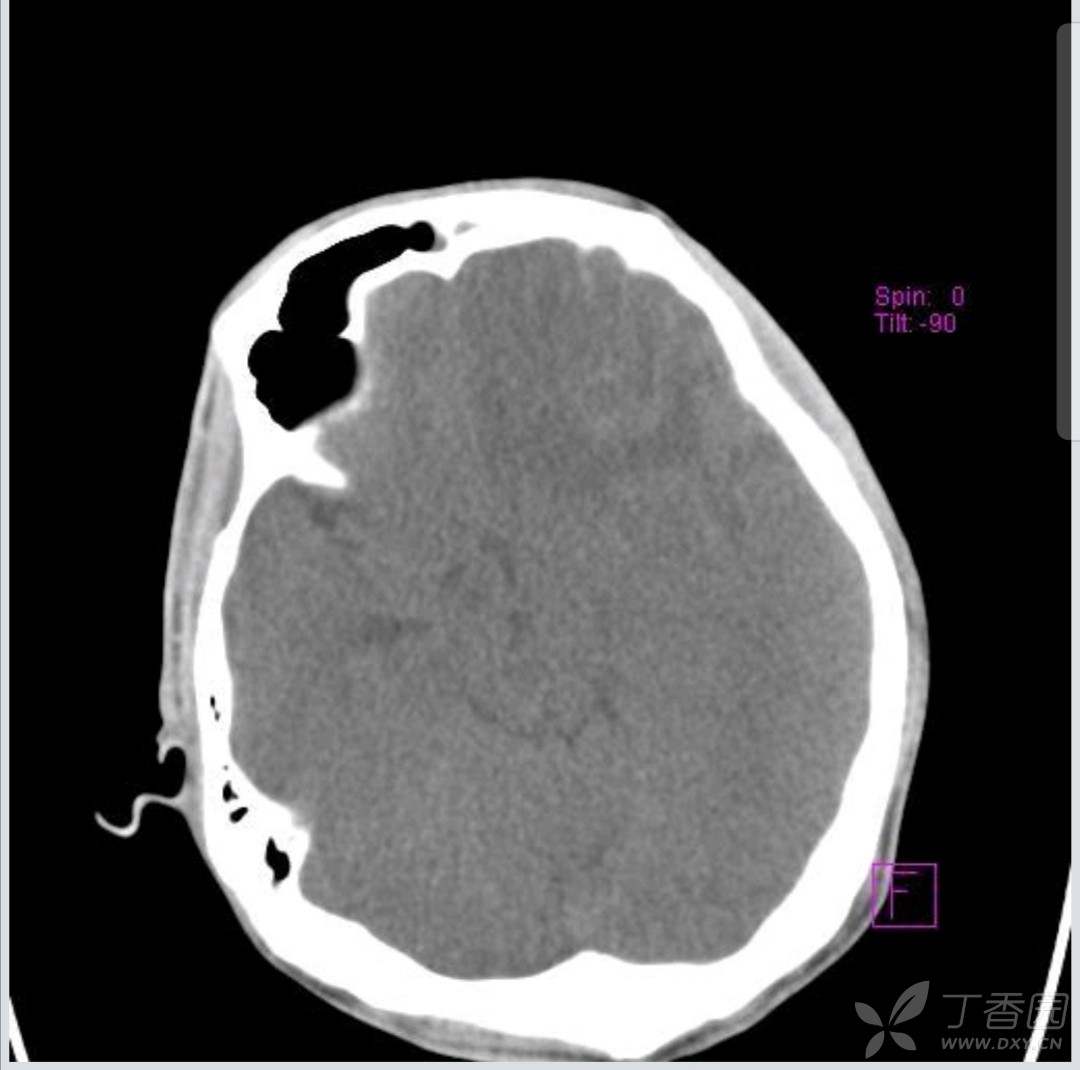

截取关键层面。两次大概在同一水平上。

抽搐后CT截取如下